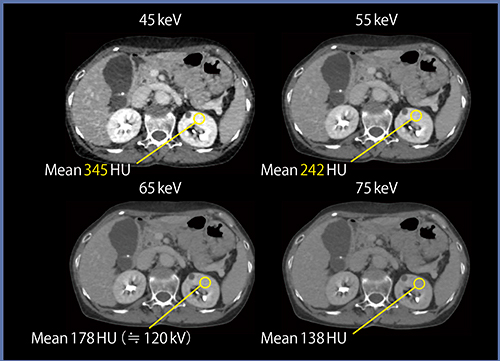

一方,仮想単色X線画像における低エネルギー画像は,造影剤コントラストの強調に有用である。仮想単色X線画像の対象エネルギーを下げていくと,ヨードの線減弱特性により造影剤のCT値が上昇する。図6に示すデータでは,45keVの画像において120kV相当画像の約2倍にまでCT値が上昇している。この時,画像ノイズが問題となるが,われわれは現在,基準物質画像からの画質改善に取り組んでいる。これにより,低エネルギー側のみならず,すべてのkeV画像における画質改善が図れるとともに,将来のCTを見据えたさらなる技術として役立つものと考えている。

図6 基準物質画像からのノイズ低減(W.I.P.)